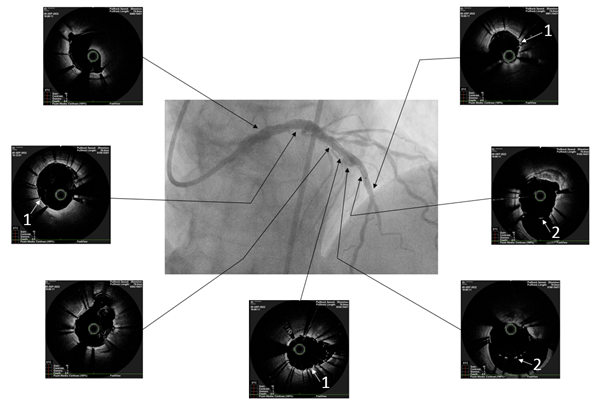

The patient underwent endovascular rotational atherectomy followed by stenting of the affected segments of the coronary arteries. The intervention was carried out under the control of optical coherence tomography (OCT). Initially, the right common femoral artery was punctured under local anesthesia and a 7F introducer was placed. Next, the guide catheter was placed at the mouth of the LCA. The coronarogram revealed 80% calcified stenosis in the terminal LCA OS with a transition to the proximal segment of the LAD and 90% calcified stenosis in the middle segment of the LAD (Figure 1). Using a microcatheter, a conductor was introduced into the apical segment of the LAD. Next, the destruction of calcified atherosclerotic plaques in the LCA and LAD was performed using the Rotablator system of rotational atherectomy (Figure 2), after which, under OCT control (Figure 3), predilatation of the stenotic areas of the LAD with a 2.25x15 mm balloon catheter was performed, followed by positioning and implantation in the area of residual stenoses in the middle segment of the LAD, the proximal segment of the LAD and the OS of the LCA of everolimus drug-eluting stents 3x38 mm and 4x38 mm, respectively. Then, post-dilatation of the stented segments with 3.5x20 mm, 4.5x15 mm balloon catheters and proximal optimization in the LCA OS with a 5x15 mm balloon catheter were performed, achieving a good angiographic result: blood flow in the TIMI-3 arteries. On the control image and OCT control, the stents were fully extended, no signs of dissection were detected, and no residual stenoses were found (Figure 4, 5).

Figure 3 Optical coherence tomography after rotational atherectomy.

White arrows indicate destroyed concentric calcification (1).